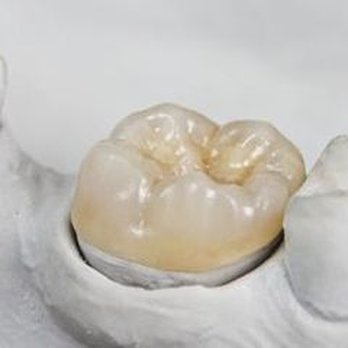

Dr. Pritpal Gill has been in practice since 2010. Dr. Gill graduated from New York University (NYU) with Honors in Implantology. Dr. Pritpal Gill is a good listener, likes talking about procedures, and takes pride in reducing pain bringing smiles back to his patients. With his experience, skills, and passion for dentistry, Dr. Gill can provide best dental care to his patients. We look forward to bringing you the latest modern dentistry delivered by a team that truly cares about you and your smile. We offer best customer care.